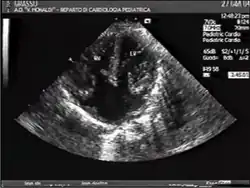

| Diagnostic method | Ultrasound and echocardiography |

AVSDs can be detected by cardiac auscultation; they cause atypical murmurs and loud heart tones. Confirmation of findings from cardiac auscultation can be obtained with a cardiac ultrasound (echocardiography - less invasive) and cardiac catheterization (more invasive). It is also possible to diagnose AVSD in-utero via routine fetal ultrasounds or, more conclusively, fetal echocardiograms.[3]